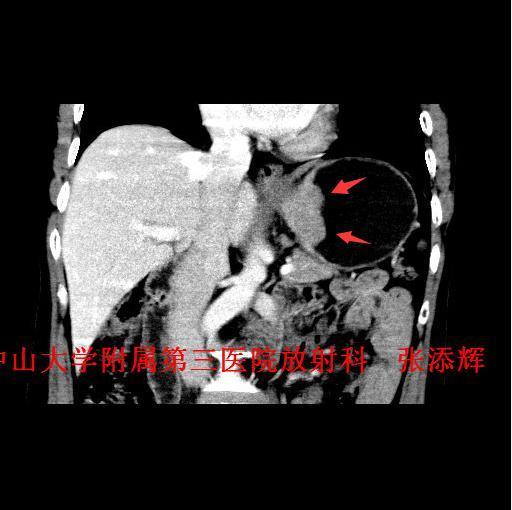

主诉:反复吞咽不畅2月余 病史:患者反复吞咽不畅2月余,吞咽固体、质硬食物时明显,伴恶心、呕吐少量食物,呕吐多在进食半小时内发生。无呕血、咯血、黑便,体重下降约4Kg。

查体:全身浅表淋巴结未触及肿大。腹平软,无压痛、反跳痛。 辅查:1、胃镜:贲门Ca?;2、上腹部CT示:贲门胃底癌,浸润胃壁全层,小网膜囊多发稍大淋巴结。

诊断:贲门癌 治疗:排除手术禁忌征后,全麻下行“腹腔镜下根治性全胃切除术”。术中及术后病理诊断为“中-低分化腺癌,浸润胃壁全层,1/61枚淋巴结转移,分期T3NIM0,ⅡB期”。

讨论:贲门癌发病率和病死率均较高,临床上其诊断主要依靠胃镜检查+病理活检,然而CT检查也是贲门癌必不可少的术前检查,术前CT不仅能了解贲门癌病变局部情况,还可以观察周围结构及远处转移的情况,特别是对于淋巴结的转移,贲门癌淋巴结转移多位于贲门旁、胃小弯、胃左动脉及腹腔动脉周围淋巴结,平时读片是应该多注意这些部位的淋巴结是否肿大。 参考文献:Stein HJ,Feith M,Siewert JR. Cancer of the esophagogastric junction [J].Surgical Oncology,2000,9(01):35-41 .doi:10.1016/S0960-7404(00)00021-9 .